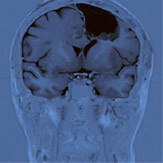

Abb. 1

MRI vor der Operation: Der Kreis kennzeichnet den grossen, hirneigenen Tumor von fast 6 cm Durchmesser im linken Stirnlappen.

Nach einem epileptischen Krampfanfall und der anschliessenden Diagnose eines grossen, hirneigenen Tumors mit über sechs Zentimetern Durchmesser im linken Stirnlappen (Abb. 1) wurde eine 52-jährige Patientin zugewiesen. Kurze Zeit darauf erlitt die Patientin einen zweiten Krampfanfall, was rasch zur Operation führte.